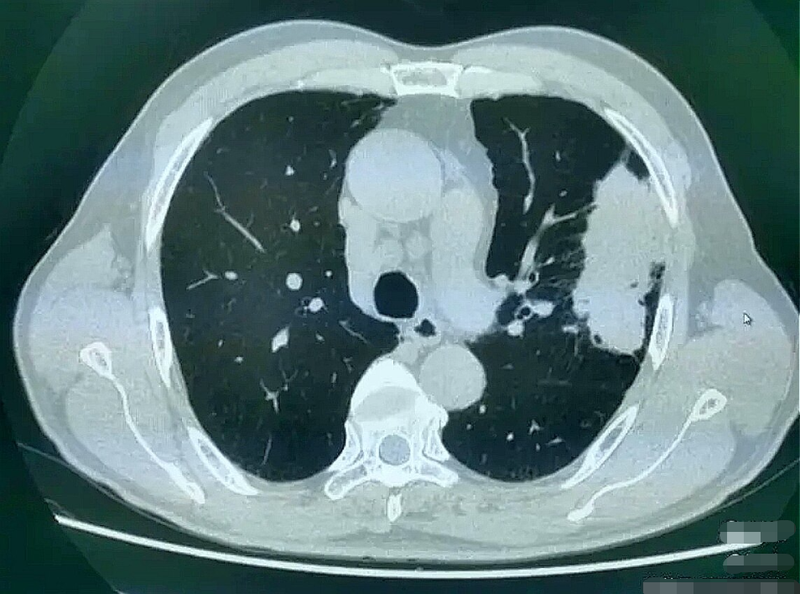

肺癌是目前最常見的惡性腫瘤,我國肺癌年發(fā)病率約為57.26/10萬,肺癌年死亡率約為45.87/10萬。臨床表現(xiàn)不一,可以咳嗽、痰中帶血或咯血、呼吸氣促、胸悶等等。對于沒有發(fā)生轉(zhuǎn)移的早期非小細(xì)胞肺癌(non-smallcelllungcancer,NSCLC),外科切除是治愈的主要手段。但是大部分患者就診時已失去外科手術(shù)機會,屬中晚期,無法手術(shù)切除,此時為控制腫瘤則需進(jìn)行綜合治療!現(xiàn)在介入醫(yī)學(xué)精細(xì)化與精準(zhǔn)化日新月異,隨著介入治療聯(lián)合靶免治療的臨床應(yīng)用,相比于過去傳統(tǒng)化療、放療及局部有創(chuàng)治療,介入治療聯(lián)合靶免治療更顯優(yōu)勢,并具有更好的生存質(zhì)量!本期講述我們在肺癌的介入治療中的小故事!老先生雖然年事已高,但英俊瀟灑的面容仍然無法隱蓋其早年創(chuàng)業(yè)成功的氣質(zhì),膝下兒女也多孝順,事業(yè)有成!雖然前些年新冠肆虐,但遠(yuǎn)在鄉(xiāng)間,空氣清新,也無大礙,仍過著富足甜蜜的生活,每天聞雞起舞,掌不離身!有一天早晨正當(dāng)氣沉丹田,準(zhǔn)備出拳時老先生突感胸悶,咳出鮮血,體力明顯不支,家人遂即送醫(yī),檢查發(fā)現(xiàn)為中晚期肺癌,全家頓時心亂如麻,不知所措!連忙趕至上海,尋求名醫(yī)指點迷津,可惜天空不作美,當(dāng)時疫情反復(fù),上海專家告訴家人疾病屬于晚期癌癥,好辦法寥寥無幾,或許中醫(yī)中藥,絕門偏方會有奇跡發(fā)生,于是膝下子女四處打聽奇方妙藥,總想做好最后一搏!我就成了他們的求醫(yī)問藥的好幫手,一是我是患者兒子的高中學(xué)長,再者,因為我跟別的醫(yī)生不大一樣,我說中晚期肺癌可以介入治療,說不定有效呢?家人一聽還有希望,便齊刷刷地出現(xiàn)在我面前,一致同意介入治療,就這樣經(jīng)過數(shù)次介入治療,患者呼吸順暢了,咳嗽減輕了,咯血消失了,CT復(fù)查左側(cè)巨大肺癌也漸漸消退,只留下纖維條索影,連雞蛋大的縱隔淋巴結(jié)也奇跡般地消聲匿跡了!介入治療讓這位年邁的患者重獲新生,他依然每天晨起練武打拳,享受著天倫之樂!經(jīng)常定期來我門診復(fù)診!這樣的病例已經(jīng)有好多例了,我真心希望能為更多的肺癌患者送去我們的努力!CT提示左肺癌伴多發(fā)縱隔淋巴結(jié)腫大經(jīng)過數(shù)次治療后左肺癌消失,連縱隔淋巴結(jié)也消聲匿跡!另一個病例右肺癌介入治療1次,腫瘤顯著縮小每周一上午:海曙區(qū)人民醫(yī)院普濟醫(yī)院介入科門診每周二上午:寧波大學(xué)附屬第一醫(yī)院介入科門診每周三上午:海曙區(qū)人民醫(yī)院石碶院區(qū)介入科門診?